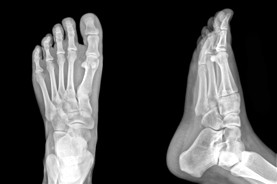

At the Edmonton Foot Institute, our Doctors are trained to specifically treat problems associated with your feet or ankles. Below are several of the most common problems that we see on a day to day basis: